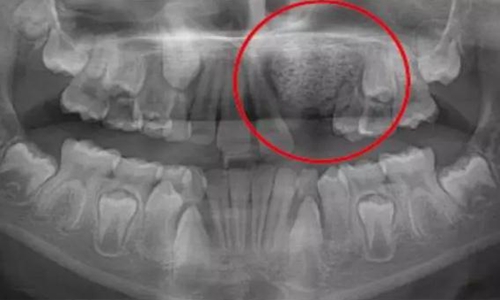

一名 23 區(qū)的9歲患者,在診所接受檢查時發(fā)現(xiàn)口內(nèi)中存在大范圍含牙囊腫[圖1]。由于上頜竇下沿出現(xiàn)大范圍突出,迫切需要接受囊腫去除手術(shù)[圖2和3]。

術(shù)前全景片[圖1]